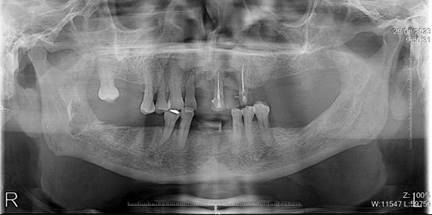

El paciente no refiere odontalgia, por lo que se presenta aparentemente asintomático al examen clínico. Dentro de las pruebas complementarias, se realizó la toma de una radiografía panorámica, donde se evidencio sobras radiolúcidas compatibles con reabsorción de la cresta ósea alveolar con patrón horizontal y vertical generalizado, también se visualizan sombras radiolúcidas alrededor de las raíces de las unidades dentales 1.2, 2.1 y 2.3, compatibles con procesos infecciosos y ensanchamiento del ligamento periodontal; además en la pieza 1.2 se complementó con una radiografía periapical en donde se observa una sombra radiopaca a nivel del tercio apical en el conducto radicular lo que podría indicar una posible calcificación y una sombra radiolúcida que rodea la raíz dental compatible con el posible ensanchamiento del ligamento periodontal; razón por la cual existe movilidad y menor soporte (Figura 2).

Figura 2. Radiografía panorámica y periapical de la pieza N.º 1.2

Elaboración: Los autores.